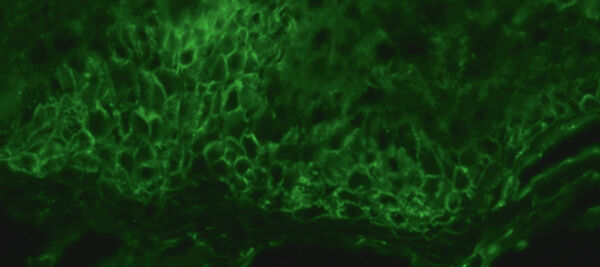

Direkte Immunfluoreszenz einer periläsionalen Hautbiopsie zeigt Ab­lagerungen von IgG an den Zell-Zell-Kontakten (interzelluläres Fluoreszenzmuster; x 250).